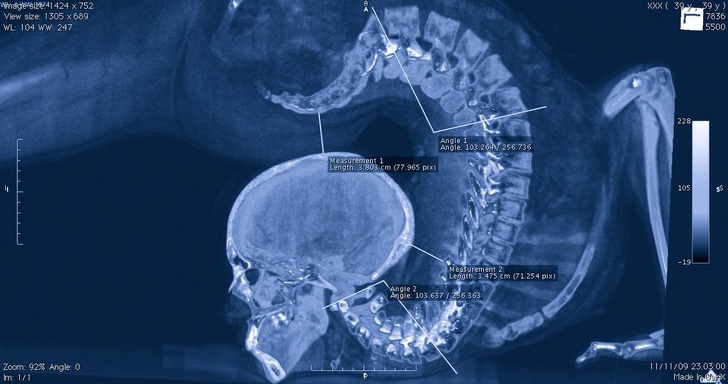

Позвоночник акробата на рентгене